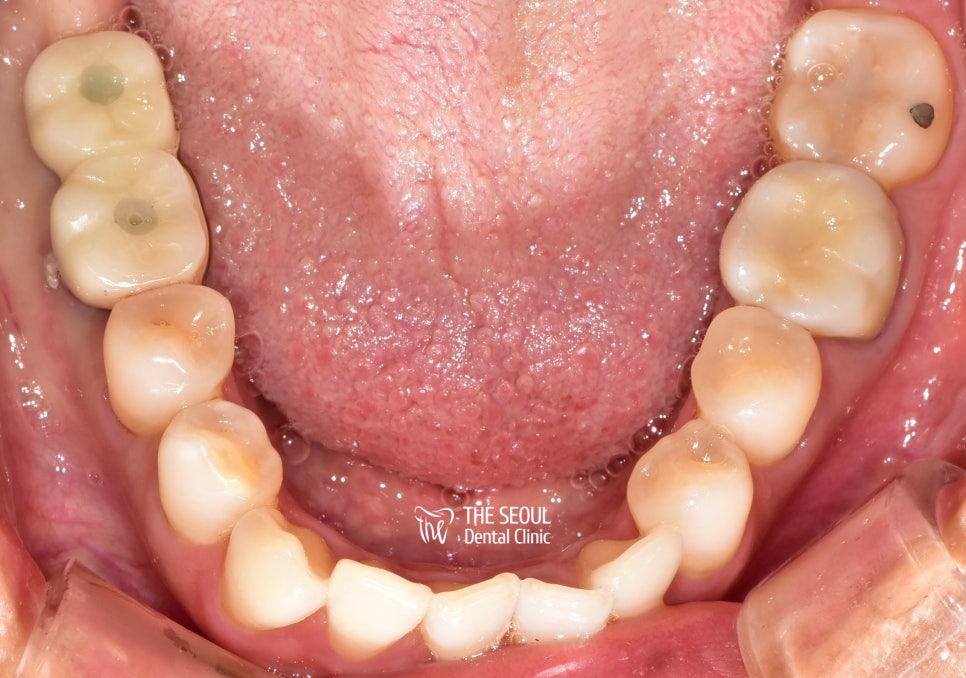

드디어 Last day!!!

완성된 크라운을 올려드리는 작업을 했습니다.

오~ 텅 비어져 있던 곳이

지르코니아로 제작된 보철이 올라가니 눈에 띄게 밝아지고

더불어 인접해 있는 치아들도 좀 더 건강해 보이네요~

외국인 치과 진료를 마치면서 너무나 만족해하셨던 환자분..

치아에 문제가 생기면 무슨 일이 있어도 여기로 오신다는데요ㅎㅎ

더불어 대한민국 기술이 뛰어나다며 극찬을 아끼지 않으셨습니다.

이렇게 만족할 만한 결과를 안겨드릴 수 있어서 다행입니다.